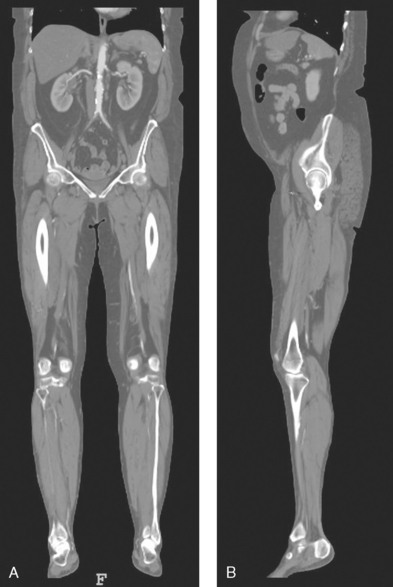

Body planes are used in computed tomography (CT), magnetic resonance imaging (MRI), and ultrasound (US) to identify the orientation of anatomic cuts or slices shown in the procedure (Fig. 3-2). Imaging in several planes is often used to show large sections of anatomy (Fig. 3-3).